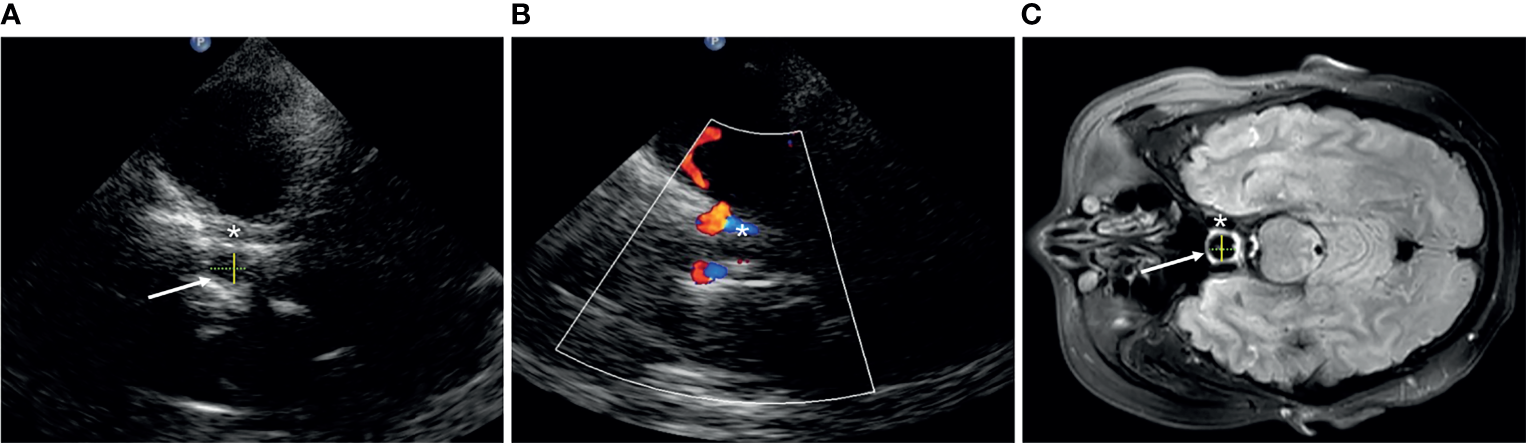

We define the transverse diameter (D1, cm) and the anterior–posterior diameter (D2, cm) of the Sella turcica as the inner side of two hyperechoic lines between the cavernous internal carotid artery and the bony anterior and posterior wall, respectively, in the axial position (Figure 1). The vertical diameter was not definite because it cannot be identified by TCS. The pituitary tumor volume (PV, cm3) = anteroposterior diameter × superior–inferior diameter × left–right diameter × 0.52, both in TCS and MRI.

Figure 1

The structure of Sella turcica (arrow) in transcranial sonography (A, B) and MRI (C). Asterisk, cavernous segment of the internal carotid artery; yellow solid line, D1; green dotted line, D2.